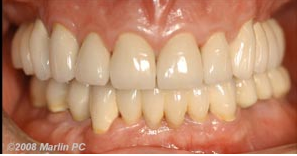

See how dental implants can improve smiles and jaw stability with these before/after photos.

[media-credit id=15 align=”alignleft” width=”297″]Implant Rejuvenation of the Jaw Before[/media-credit]Implant Rejuvenation of the Jaw After